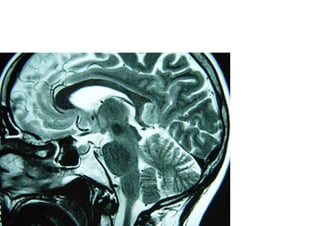

Vascular

Hemorragica

Isquemica

Neoplasica

Degenerativa

Traumatica